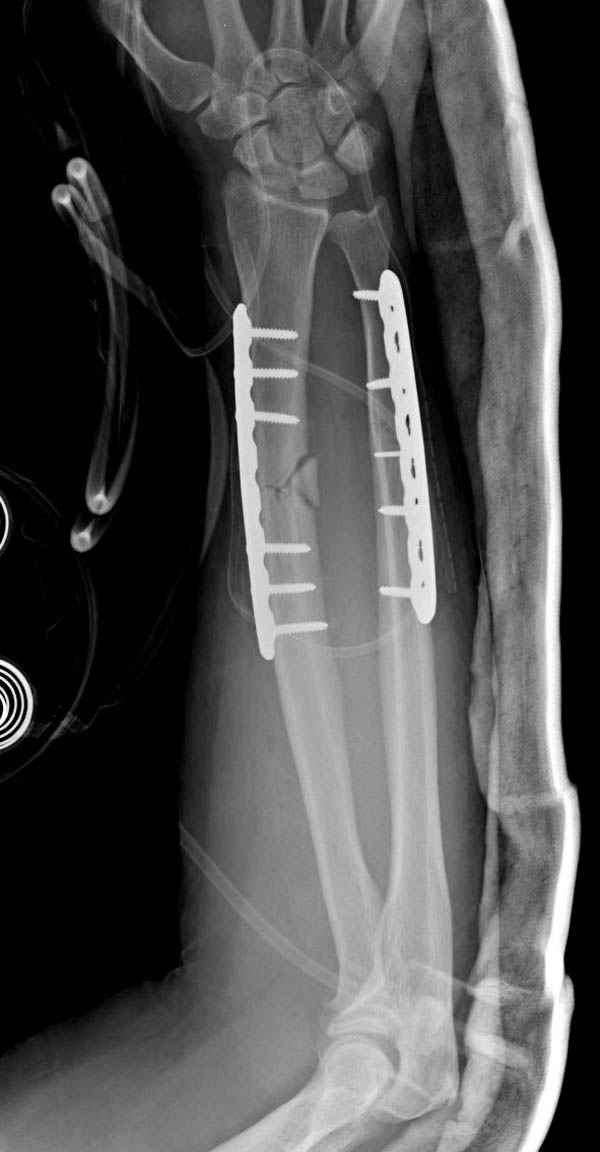

Второй случай, для лечения перелома проксимального

плеча применили пластину "Hand Innovation"

http://www.handinnovations.com/pdf/S3_technique.pdf

Пластина имеет преимущества перед другими "Locking

Implants", потому что пластину можно уложить намного ниже чем другие пластины и имеется возможности проведения шурупов под 130 градусным углом, таким образом можно уменьшить операционный разрез в проксимальной части.

Прооперирован вчера на 13 день после поступления.

Больному 41 и из-за гемодинамической нестабильности в течение первых 7 дней был в реанимации под интубационной седацией.

Кроме перелома плеча у больного старый дистракционный перелом T12-L1 оперированный когда-то и кем-то, открытый перелом костей предплечья, который был прооперирован в ночь поступления, после I&D (хирургической обработки). Из-за разрыва селезенки при поступлении травма хирургами произведено удаление.

Извиняюсь за качества снимков, обычный больной в 300 фунтов, портативным ренген аппаратом не пробить.